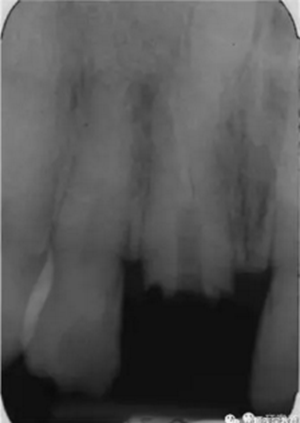

本例患者為男性,53歲,由于右上頜中切牙疼痛,在蘇格蘭的格拉斯哥口腔醫(yī)院就診。根管治療后1年來牙齒出現自發(fā)性疼痛。檢查發(fā)現患者冠部修復體3周前丟失,未發(fā)現竇道,牙面較多部位探診時患者較敏感,說明牙齒仍為活髓,可以修復?;颊呱眢w狀況良好。影像學顯示,患牙根尖彎曲處充填不充分,根尖周有陰影,還發(fā)現在右上頜中切牙的根尖部有一倒置的額外牙顯影,周圍牙周膜寬度正常。

圖1. 治療前患牙根尖周顯影